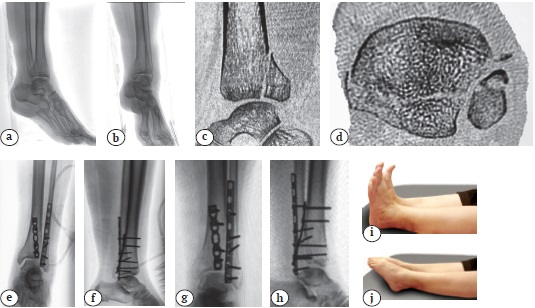

Отличный результат хирургического лечения пациентки с переломом типа 44-В3 с использованием описанного способа представлен на рисунке 3.

Рис. 3. Отличный результат хирургического лечения пациентки 58 лет с переломом типа 44-В3 после остеосинтеза:a, b — первичные рентгенограммы в прямой и боковой проекциях;c, d — данные КТ, показывающие размер заднего края ББК; e, f — послеоперационные рентгенограммы в прямой и боковой проекциях — анатомичная репозиция голеностопного сустава; g, h — рентгенограммы через 3 мес. после травмы — консолидация переломов; i, j — функциональный результат в срок 12 мес. после травмы